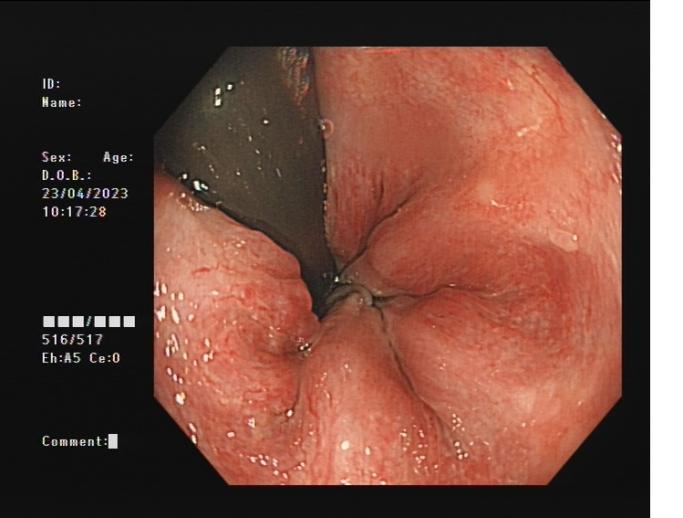

3b2d4fd666c540e5a8957f178dfb0b6b.Jpeg38cdda0ed1d245cfa077b1a308a229ca.Jpeg

內(nèi)痔                    內(nèi)鏡下內(nèi)痔硬化治療

內(nèi)鏡下內(nèi)痔硬化術(shù):治療I-Ⅲ度內(nèi)痔伴有內(nèi)痔相關(guān)癥狀;I~Ⅲ級(jí)內(nèi)痔飲食及藥物治療無(wú)效;內(nèi)痔手術(shù)后復(fù)發(fā),肛門反復(fù)手術(shù)后不能再次手術(shù);恐懼外科手術(shù),不愿意接受手術(shù)治療;高齡、高血壓、糖尿病和嚴(yán)重的系統(tǒng)性疾病,不能耐受外科手術(shù)等。

3ec63f6bdf6c49908576319b43de8ed5.Jpeg793b9b4fe5dd4c639a19025be7c58d78.Jpeg

內(nèi)痔                   內(nèi)鏡下套扎術(shù)

內(nèi)鏡下內(nèi)痔套扎術(shù):治療內(nèi)痔并脫出和(或)出血等癥狀,包括II、Ⅲ度內(nèi)痔等。